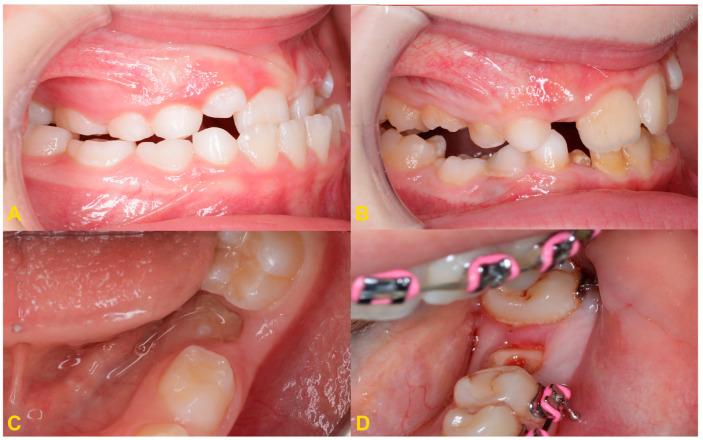

The gradual movement of a tooth away from the occlusal plane is called infraocclusion or reinclusion. Reincluded teeth are most often deciduous molars, and permanent teeth are less frequently affected. Depending on the level of the infraocclusion, the severity of the disorder is classified as mild, moderate, or severe. The etiology of the phenomenon is not fully known. Tooth submerging can lead to serious complications, such as abnormal position of adjacent teeth, displacement of the bud of the permanent successor, shortening of the dental arch, or developmental disturbances of alveolar process. Early diagnosis of the tooth infraocclusion and regular monitoring of its progression help to avoid serious permanent sequelae. The treatment of reinclusion often involves only observation. However, in some cases, the therapeutic procedure requires interdisciplinary treatment by specialists from various fields of dentistry. This study presents current methods of diagnosis and treatment of patients with submerged teeth.

牙齿逐渐离开咬合平面的运动称为低位咬合或再嵌入。再嵌入的牙齿多为乳牙,恒牙则较少受到影响。根据低位咬合的程度,疾病的严重程度分为轻度、中度和重度。该现象的病因尚未完全清楚。牙齿埋没可导致严重并发症,如邻牙位置异常、恒牙胚萌出受阻、牙弓缩短或牙槽骨发育障碍。早期诊断牙齿低位咬合并定期监测其进展有助于避免严重的永久性后遗症。再嵌入的治疗通常仅涉及观察。然而,在某些情况下,治疗过程需要由来自不同牙科领域的专家进行跨学科治疗。本研究介绍了目前诊断和治疗埋藏牙患者的方法。